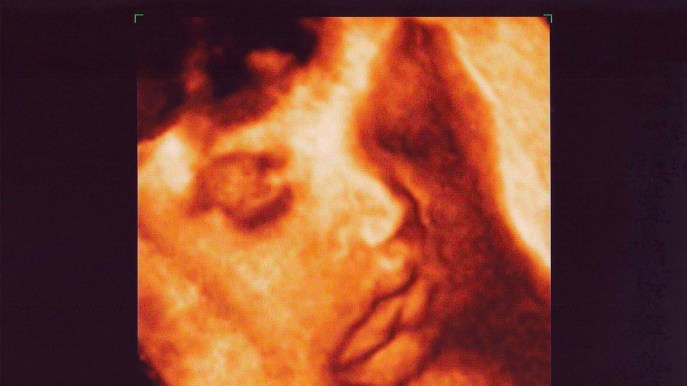

Fortunatamente la tecnologia ha sviluppato numerose soluzioni utili a indagare sullo stato di salute e sviluppo del feto. Tra le più emozionanti e suggestive spiccano le ecografie tridimensionali e quadridimensionali, in 3D o 4D, che mostrano con precisione i tratti somatici del piccolo quando è ancora dentro la pancia della mamma.

Le ecografie ostetriche in 3D e 4D stanno riscuotendo un enorme successo in tutto il mondo, perché permettono di osservare in diretta il bambino nel ventre della futura mamma, offrendo immagini tridimensionali e quadridimensionali realistiche ed emozionanti.

Grazie a questo esame è possibile guardare il feto che si muove, apre la bocca o addirittura che si succhia il dito. L’impatto è molto forte e le emozioni di gioia travolgono tutti i genitori, lasciandoli a bocca aperta davanti a una vera e propria fotografia del loro piccolo.

La qualità delle immagini dipende poi da diversi fattori, come la posizione del feto e lo spessore della parete addominale della mamma: se il tessuto adiposo è sottile, l’ecografia offre migliori risultati. Inoltre, immagini di qualità vengono registrate quando il feto si rivolge alla sonda, mentre il cordone, gli arti e la placenta sono poco visibili.